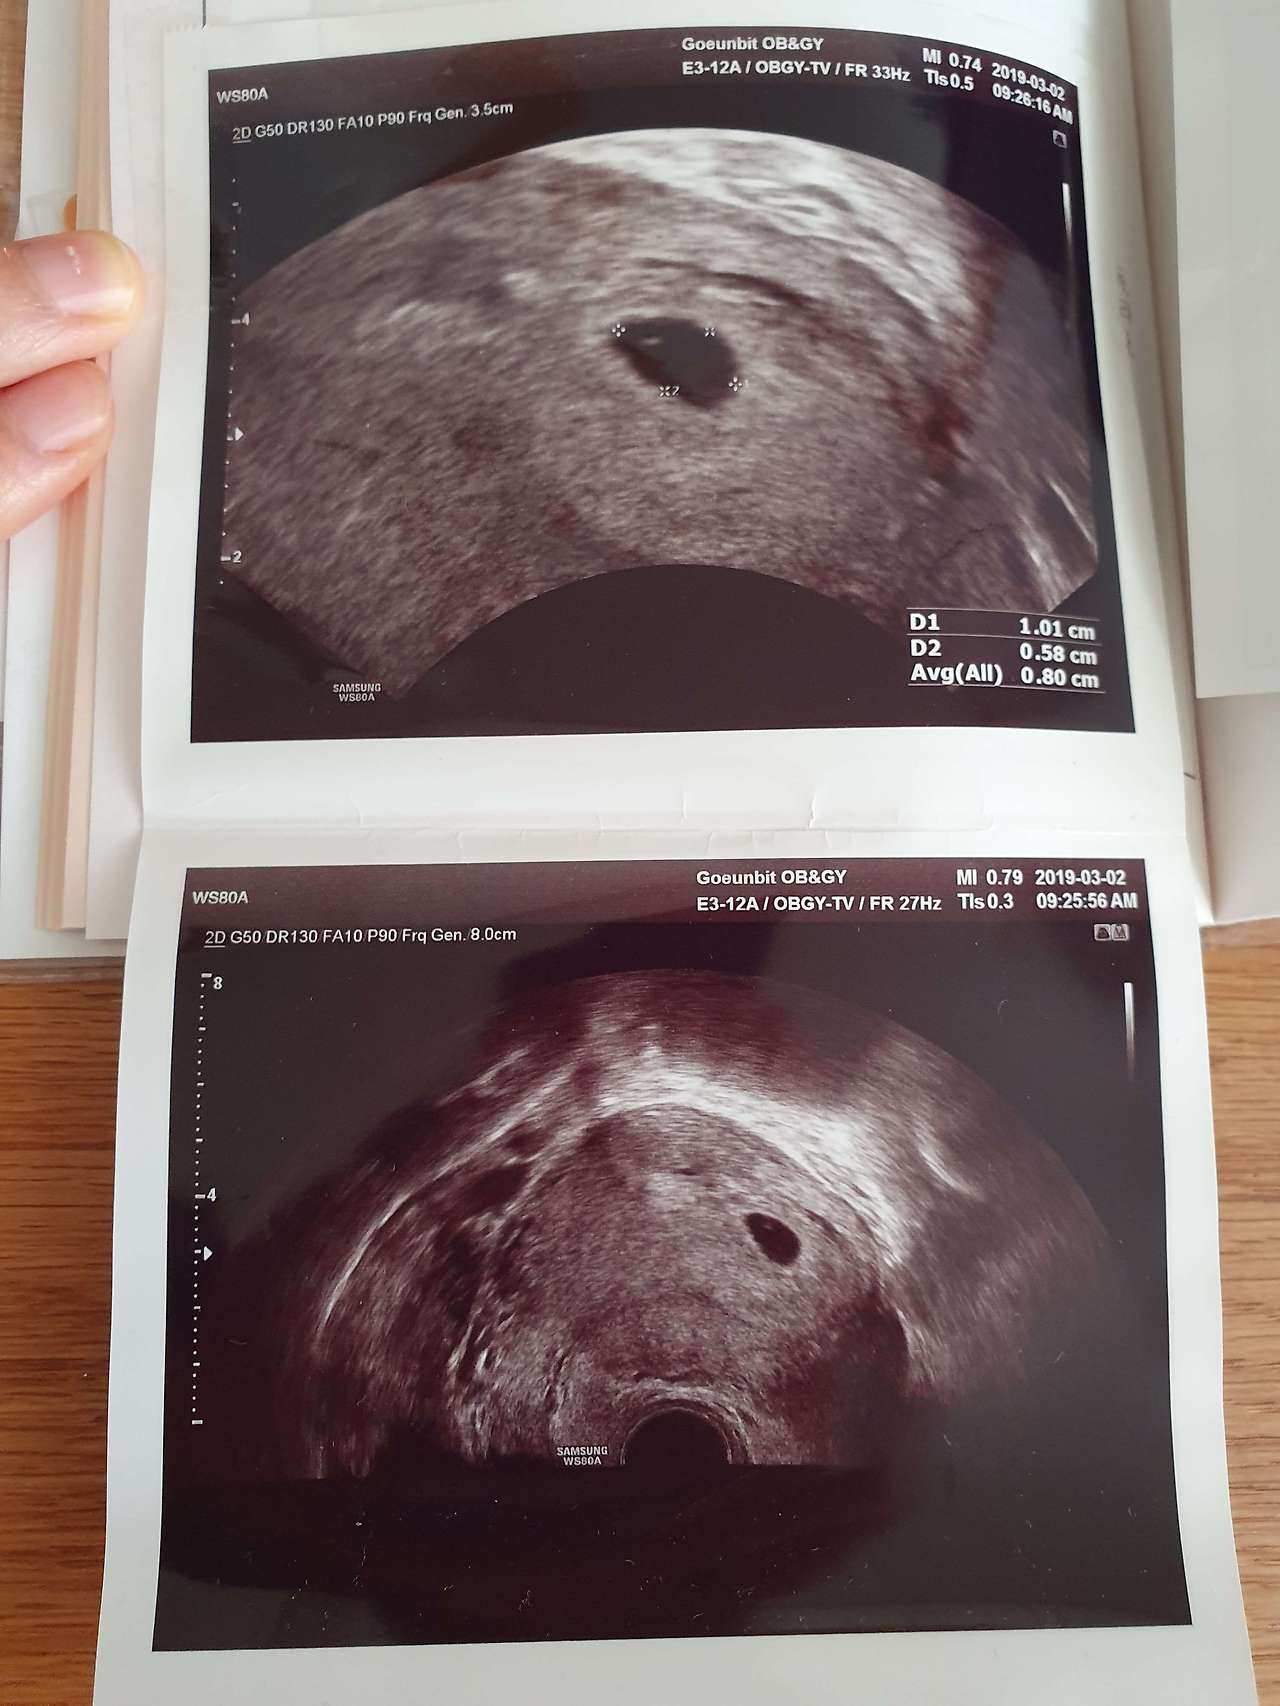

만나기로 한 당일이 되었다. 그날은 하루 종일 어색함과 이상함과 긴장의 연속이었다. 병원 접수처에서부터 그랬다. 간호사가 어떻게 왔냐는데 뭐라고 해야 할지 몰라 답을 못했다. 옆에 있던 남편이 아니었으면 어버버 하며 서있을 뻔했다. 진료실에서 '축하합니다' 하는 의사의 말에도 굳어버렸다. 임신인지 몰랐던 것도 아닌데 의사의 확진을 받고 초음파 사진을 받아 드니 기분이 묘해졌다. 이상한 기분은 갈수록 더했다. 멀리 사시는 시부모님께는 우선 전화로 소식을 알렸는데 시부모님이 말문이 막히는 바람에 우리도 할 말이 없어 전화를 끊어야 했다. 알고 보니 결혼 후 5년이나 손주를 간절히 기다리던 시부모님은 막상 임신 소식을 접하니 실감이 안 나 말문이 막혔다고 했다. 시부모님의 반응을 보니 친정 부모님께 말씀드릴 일이 더 걱정됐다.

이럴 땐 남편에게 떠넘겨야지. 식당에 도착하고 나니 더 긴장이 돼서 남편에게 초음파 사진을 주고 얘기를 하라고 했다. 남편도 긴장을 했는지 '근데 나 얘기는 잘 못하겠어.'라고 했다. 그 와중에도 초음파 사진이 구겨질까 봐 가방 속 책을 꺼내 그 사이에 고이 넣고 책을 무릎 위에 고이 올려뒀다.

4.jpg 지금은 산모수첩에 붙어있는 당시의 초음파 사진. 5주 차라 아직 아기는 안 보이고 아기집만 보인다.